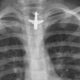

Sin embargo, el pulso paradójico se presenta en escenarios en los que el corazón enfrenta obstáculos en su capacidad de llenarse adecuadamente durante la inspiración. Esto ocurre en condiciones médicas como el taponamiento cardíaco y la pericarditis constrictiva. En el taponamiento cardíaco, la acumulación de líquido en el espacio pericárdico ejerce presión sobre el corazón, limitando su expansión durante la inspiración y reduciendo la cantidad de sangre que puede recibir. En la pericarditis constrictiva, la rigidez del pericardio impide la expansión normal del corazón, causando efectos similares.